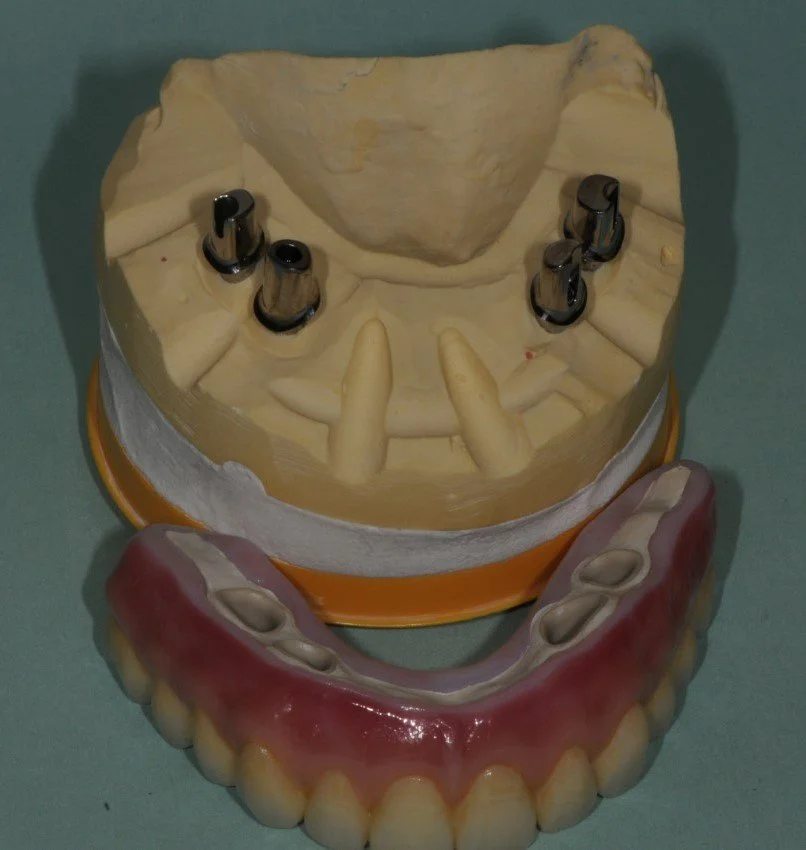

A plaster model with replicas of the implant fixtures and a photo of the base of the implant denture. The base was made of titanium, pink acrylic resin and acrylic denture teeth.

A view of the back of the implant denture showing the 4 housings for the screws used to secure the denture to the implant fixtures.

After these small screws are torqued to 35 N.cm the access openings are filled with composite resin filling material. The patient needs to return every 6 months or more to have the denture removed and professionally cleaned by a Dentist.

A gap between the pink resin and the implant fixtures, these gaps are used to allow the patient to clean around the implants using threaded Superfloss and other hygienic cleaning aids.